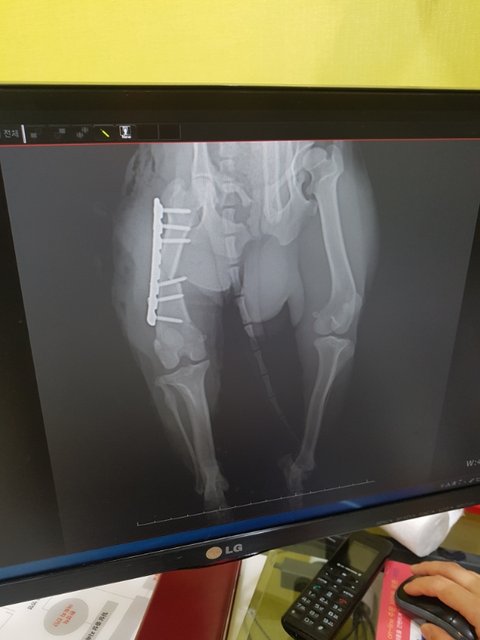

뒷다리골절 수술했습니다

우리 노아가 씩씩하게 수술을 받고 깨어났습니다

심장사상충 때문에 마취에서 못 깨어날까봐 얼마나 두려운 시간을 보냈는지 모르겠습니다

이제 한고비 넘겼습니다

회복 잘해서 사상충치료도 잘 받을수있도록 케어 잘 하겠습니다